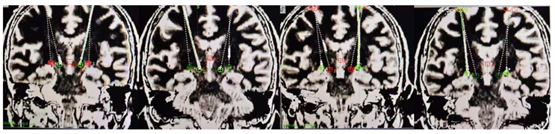

手术的成功离不开精准的术前规划和精细的术中操作。团队通过术前MRI与CT影像融合技术,结合专业手术计划系统,精准确定手术靶点和复杂路径。最终,仅通过两个直径14mm的骨孔,就成功完成了双侧4根刺激电极的精准植入,同时覆盖双侧STN/GPi靶点。术后重建影像显示,4根电极均“十环”命中目标靶点,手术过程十分顺利。